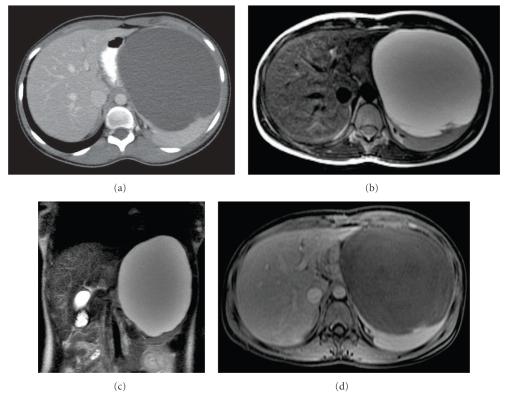

Splenic cysts are rare entities and are classified as true cysts or pseudocysts based on the presence of an epithelial lining. Congenital nonparasitic true cysts can be epidermoid, dermoid, or endodermoid, present at a young age, and are commonly located in the upper pole of the spleen. Surgical treatment is recommended for symptomatic, large (more than 5 cm), or complicated cysts. Depending on cyst number, location, relation to hilus, and the major splenic vessels, the surgical options include aspiration, marsupialization, cystectomy, partial cystectomy (decapsulation), and partial or complete splenectomy. Laparoscopic techniques have now become the standard approach for many conditions, including the splenic cysts, with emphasis on the spleen-preserving minimally invasive operations. We present the successful extended partial laparoscopic decapsulation of a giant epidermoid splenic cyst in a young female patient that, although asymptomatic, was unfortunately followed by complete splenectomy five days later due to a misinterpreted abdominal CT suggesting splenic postoperative ischemia.

脾囊肿是罕见的疾病,根据是否存在上皮衬里可分为真性囊肿或假性囊肿。先天性非寄生虫性真性囊肿可以是表皮样囊肿、皮样囊肿或内胚层样囊肿,发病年龄较轻,通常位于脾的上极。对于有症状、较大(超过5厘米)或复杂的囊肿,建议进行手术治疗。根据囊肿数量、位置、与脾门的关系以及主要脾血管情况,手术选择包括穿刺抽吸、袋形缝合术、囊肿切除术、部分囊肿切除术(去包膜)以及部分或全脾切除术。腹腔镜技术现已成为包括脾囊肿在内的许多疾病的标准治疗方法,重点是保留脾脏的微创手术。我们报告了一名年轻女性患者成功进行的扩大性部分腹腔镜脾囊肿去包膜手术,该囊肿虽无症状,但不幸的是,术后五天因腹部CT解读错误提示脾术后缺血而进行了全脾切除术。